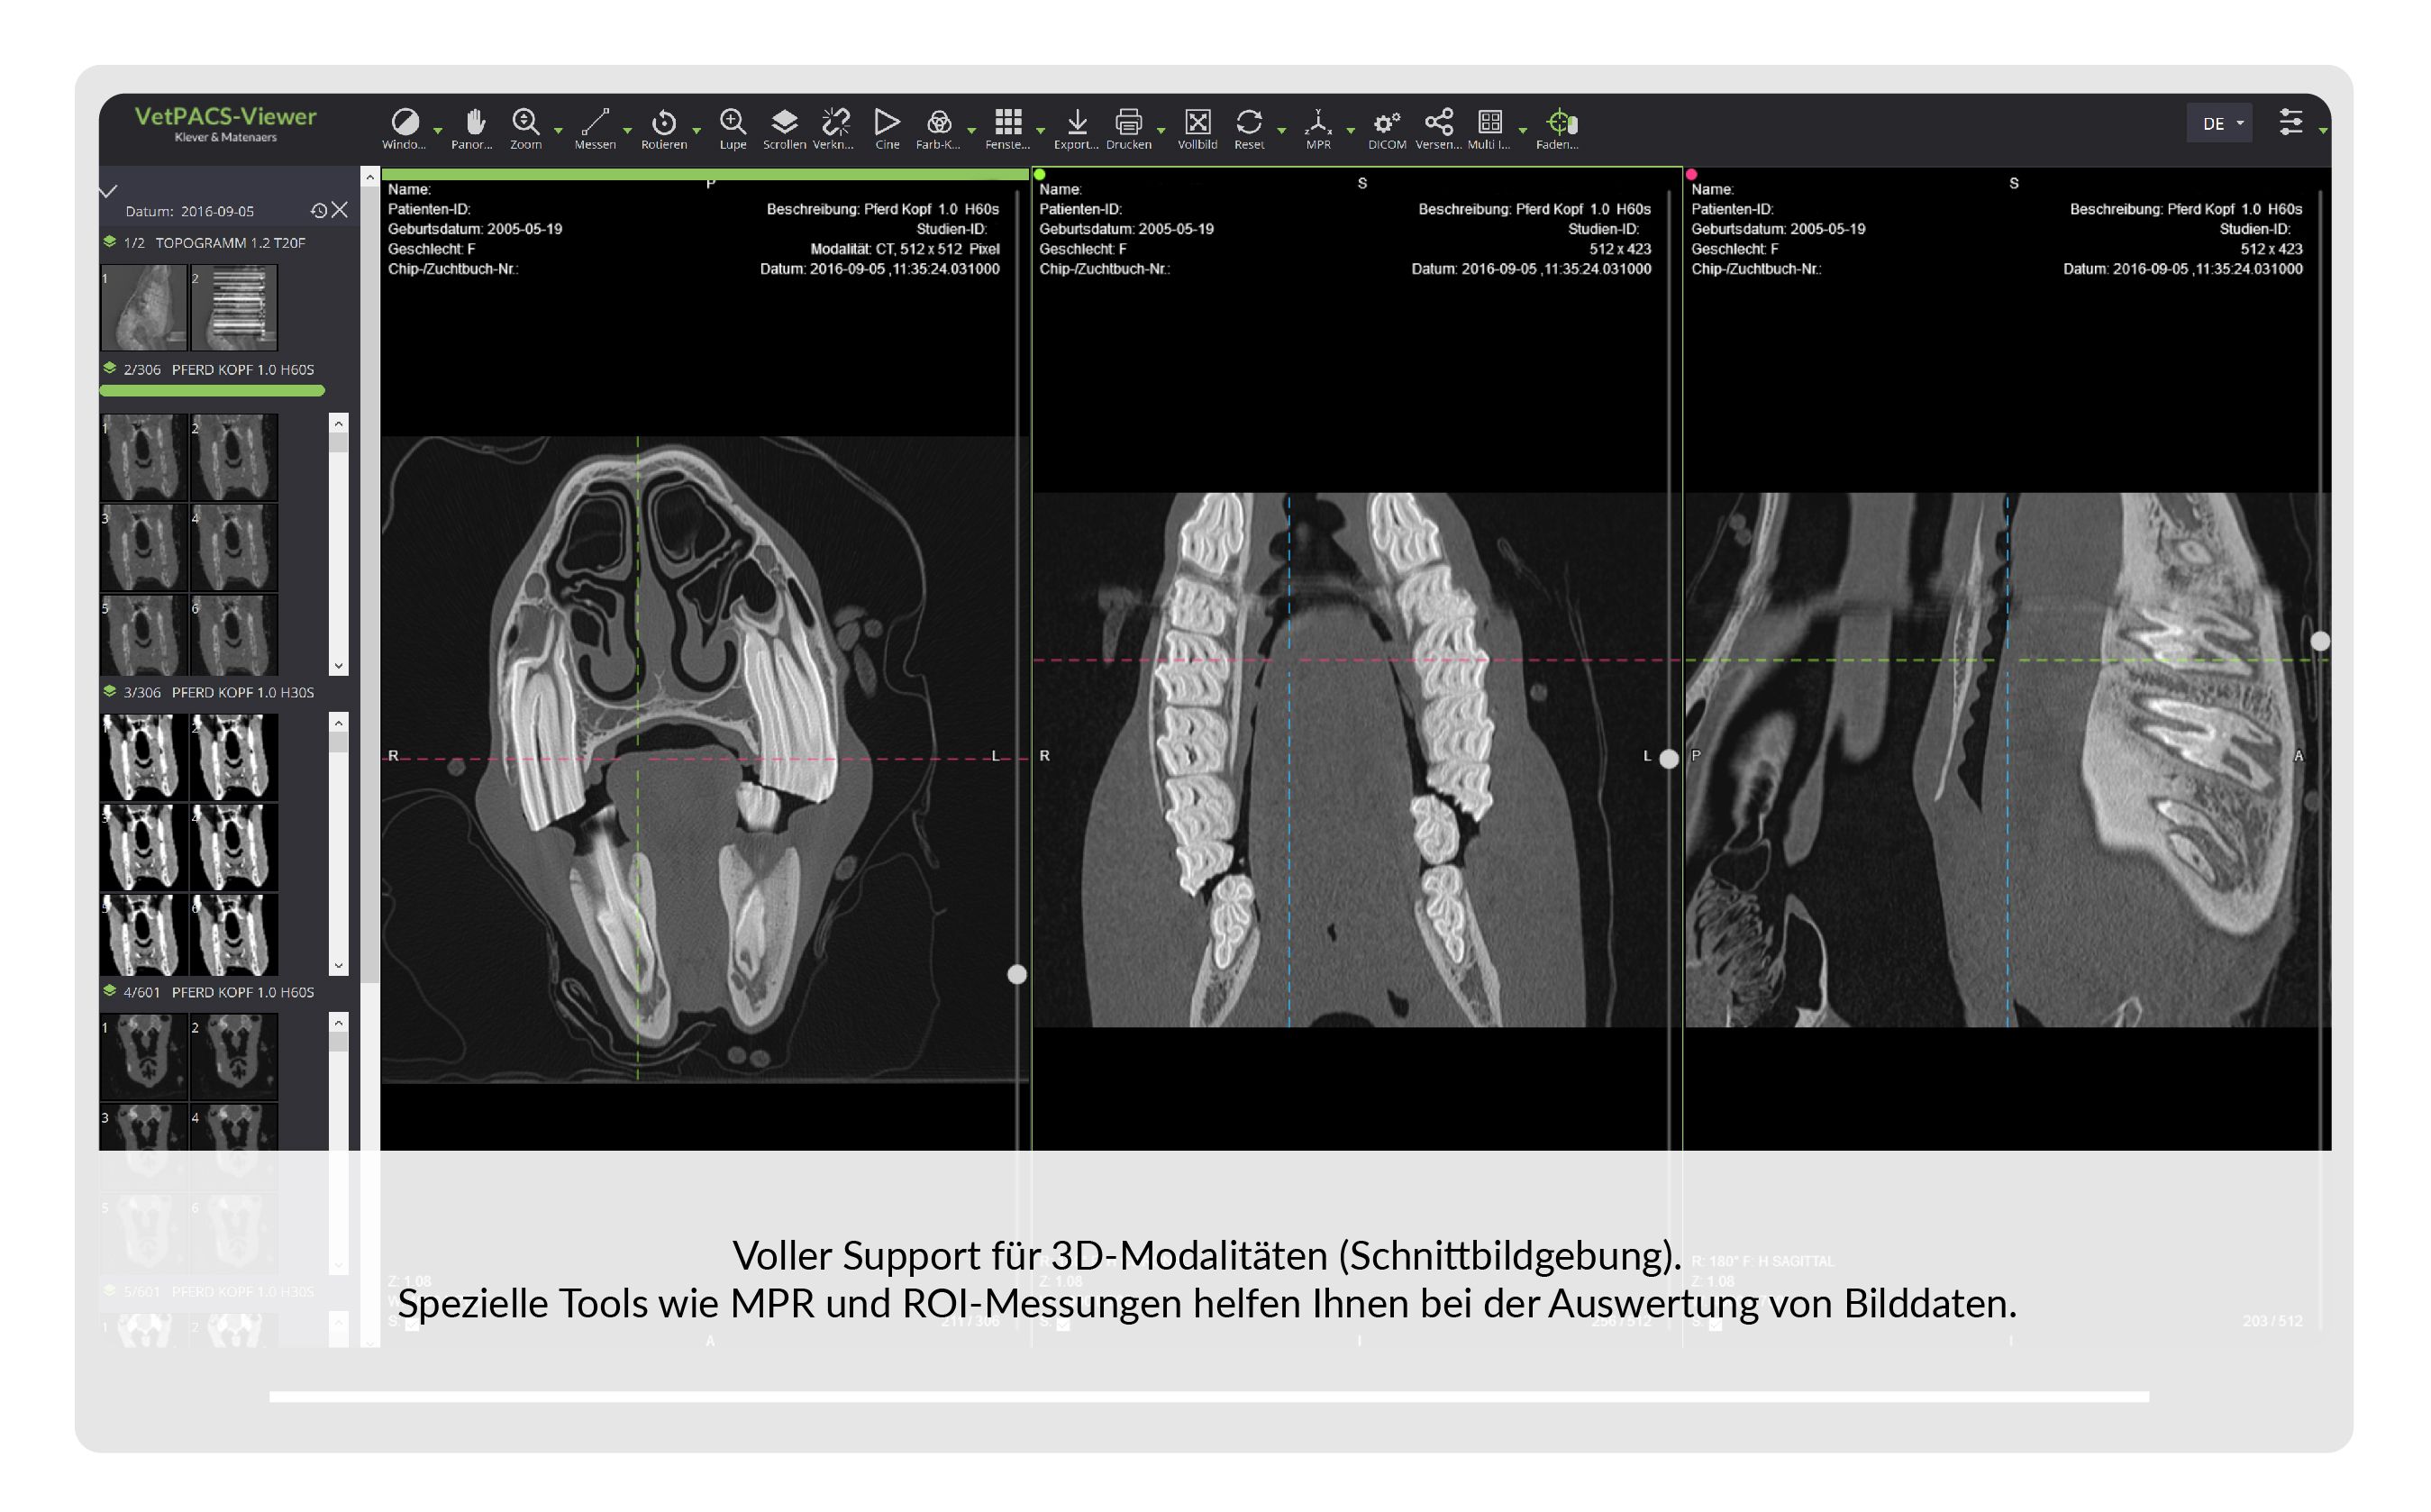

VetPACS

Unsere Lösung zur sicheren Archivierung, Befundung und Kommunikation von medizinischen Bildern und Daten.

| ✓ | Alle Funktionen sind auf veterinär-spezifische Anforderungen optimiert. |

| ✓ | Der integrierte DICOM-Viewer dient zur Betrachtung aller im VetPACS archivierten Daten. |

| ✓ | Volle Unterstützung für Schnitt-bildgebung wie CT/MRT, auf Wunsch mit obliquer MPR und 3D Rendering. |